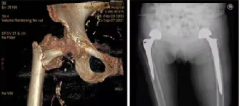

黄石有色医院为九旬老太成功换髋

近日,在黄石有色医院外二科,患者72岁的儿子握着外二科曾仁洪主任的手激动地说:感谢有色医院骨科给了她第三次生命,真没想到我96岁的老母亲还能再站起来!。 家住湖北黄石市新下陆96岁高龄的曾老太不慎将右股骨头摔断。5年前,时年91岁的曾老太因左侧股骨